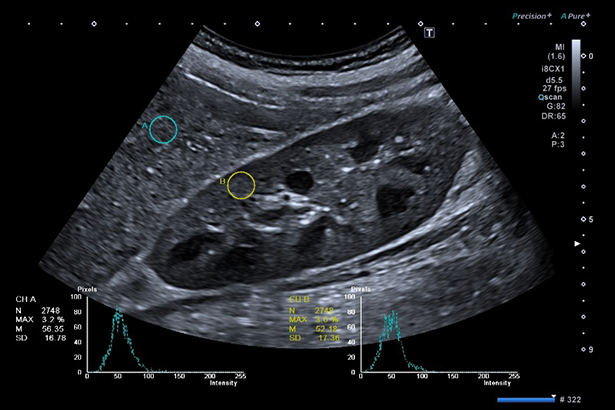

對于在 B 模式/CHI 模式下獲取的圖像,可以在兩個位置同時測量 ROI 內部的像素數(shù),平均灰度,標準偏差及其灰度分布并圖形顯示。可應用于肝,腎對比度比較中。